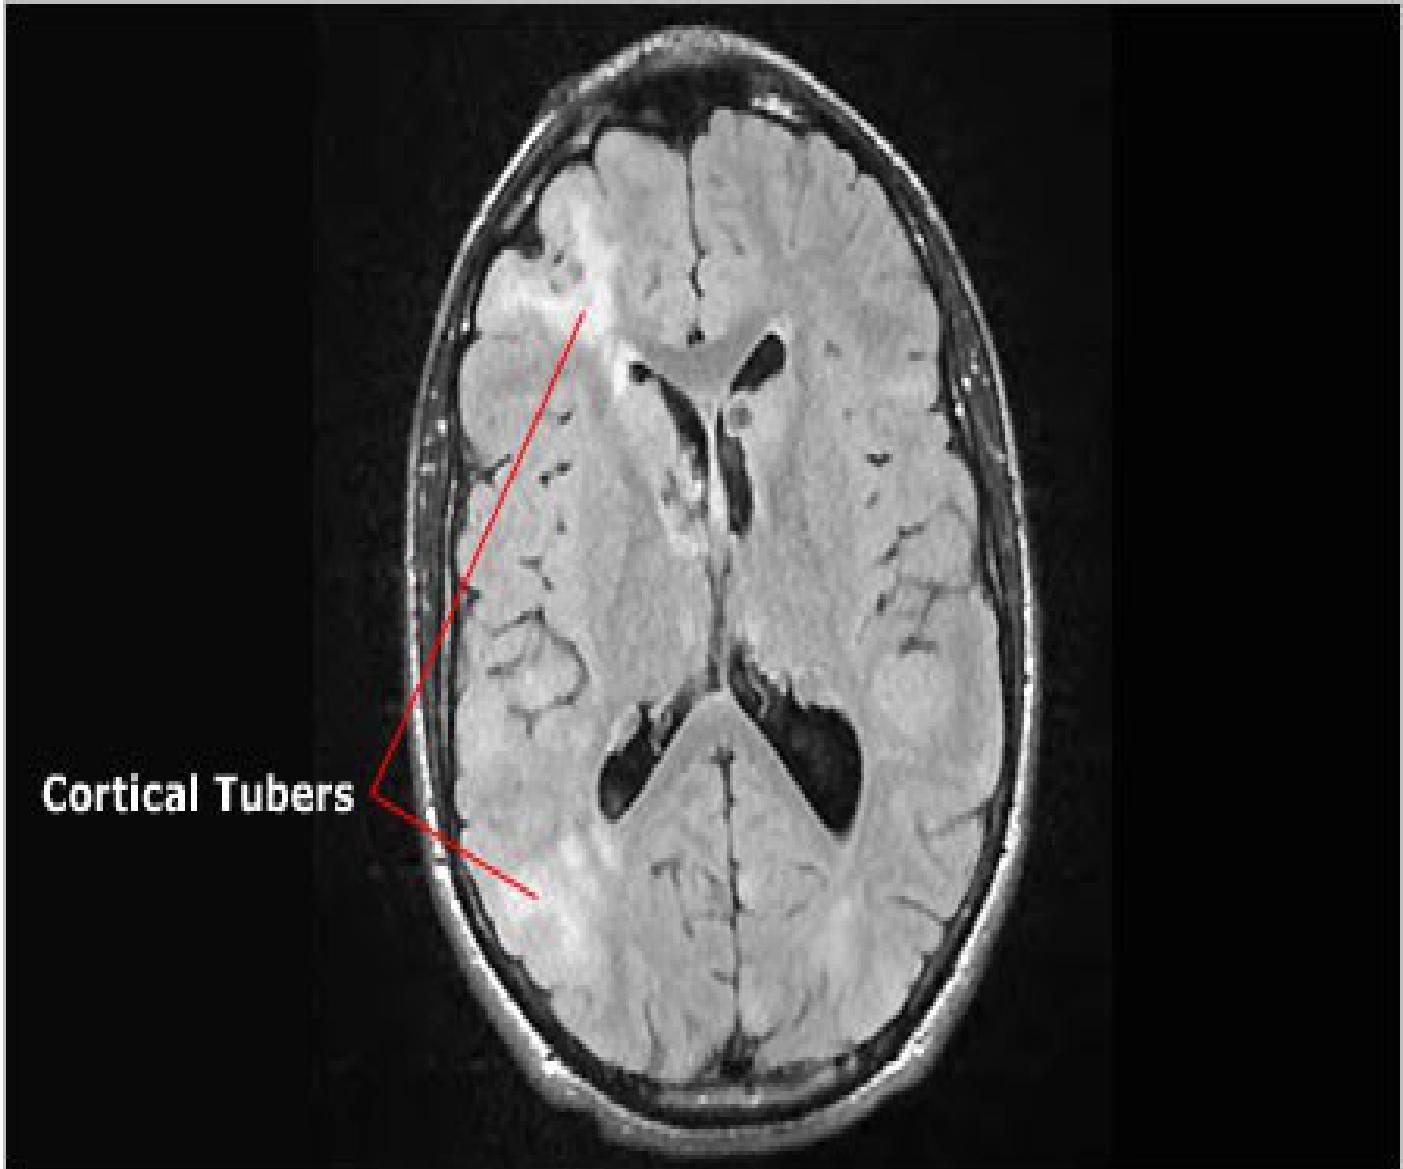

- Cortical Tubers: Brain lesions (Cortical dysplasias).

Cortical tubers: